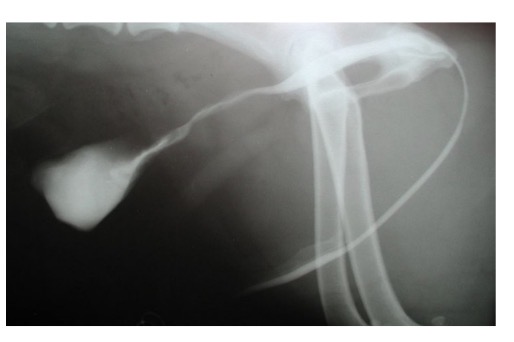

Radiography - plain, positive contrast urethrography

What can positive contrast radiography detect in urethral obstruction

Displaced bladder, radiolucent calculi, soft tissue lesions